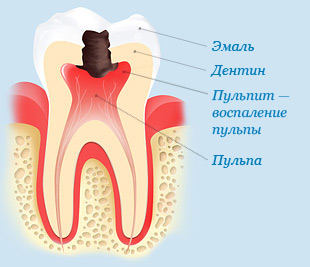

Если человек знает хоть самые основные признаки кариеса зубов, то можно избежать весьма серьезных последствий.

Больно ли лечить пульпит?

Многие стоматологические проблемы появляются именно из-за страха. Лучше полечить зуб на начальном этапе, чем потом обладать чувством страха перед креслом.